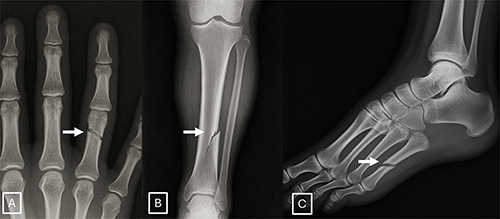

Images (JPG, TIF):

Figure 3. Anatomy-matched real and GPT-4o-generated radiographs: (A) real and (B) GPT-4o-generated posteroanterior chest radiographs, (C) real and (D) GPT-4ogenerated lateral cervical spine radiographs, (E) real and (F) GPT-4o-generated posteroanterior hand radiographs, and (G) real and (H) GPT-4o-generated lateral lumbar spine radiographs. The pairs demonstrate that GPT-4o can produce radiographically plausible images across different anatomic regions.